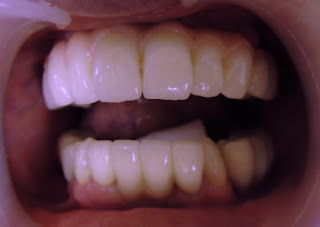

既に上下臼歯部は全てTEKに置き換わっていることや、これまでの他院での治療などが原因で最低限の侵襲でということで、シェルタイプで誘導することになりました。

座位での「噛んでみましょう」の図です

「では、もう少し前で噛んでみましょう」の図です

「大丈夫そうです」と、患者さん

患者さんに具合を伺うと、「説明していただいたことが凄く良く分かります、大丈夫そうです」だそうです。

後日両側のバイト状態を確認しながら、状態を観察できればと思っています。

そのときは、偏位に対する本人の受け入れ具合の確認に合わせて、ダイレクトボンディングによる犬歯誘導の確立をしてもらい、次のステップへ移行する予定です。